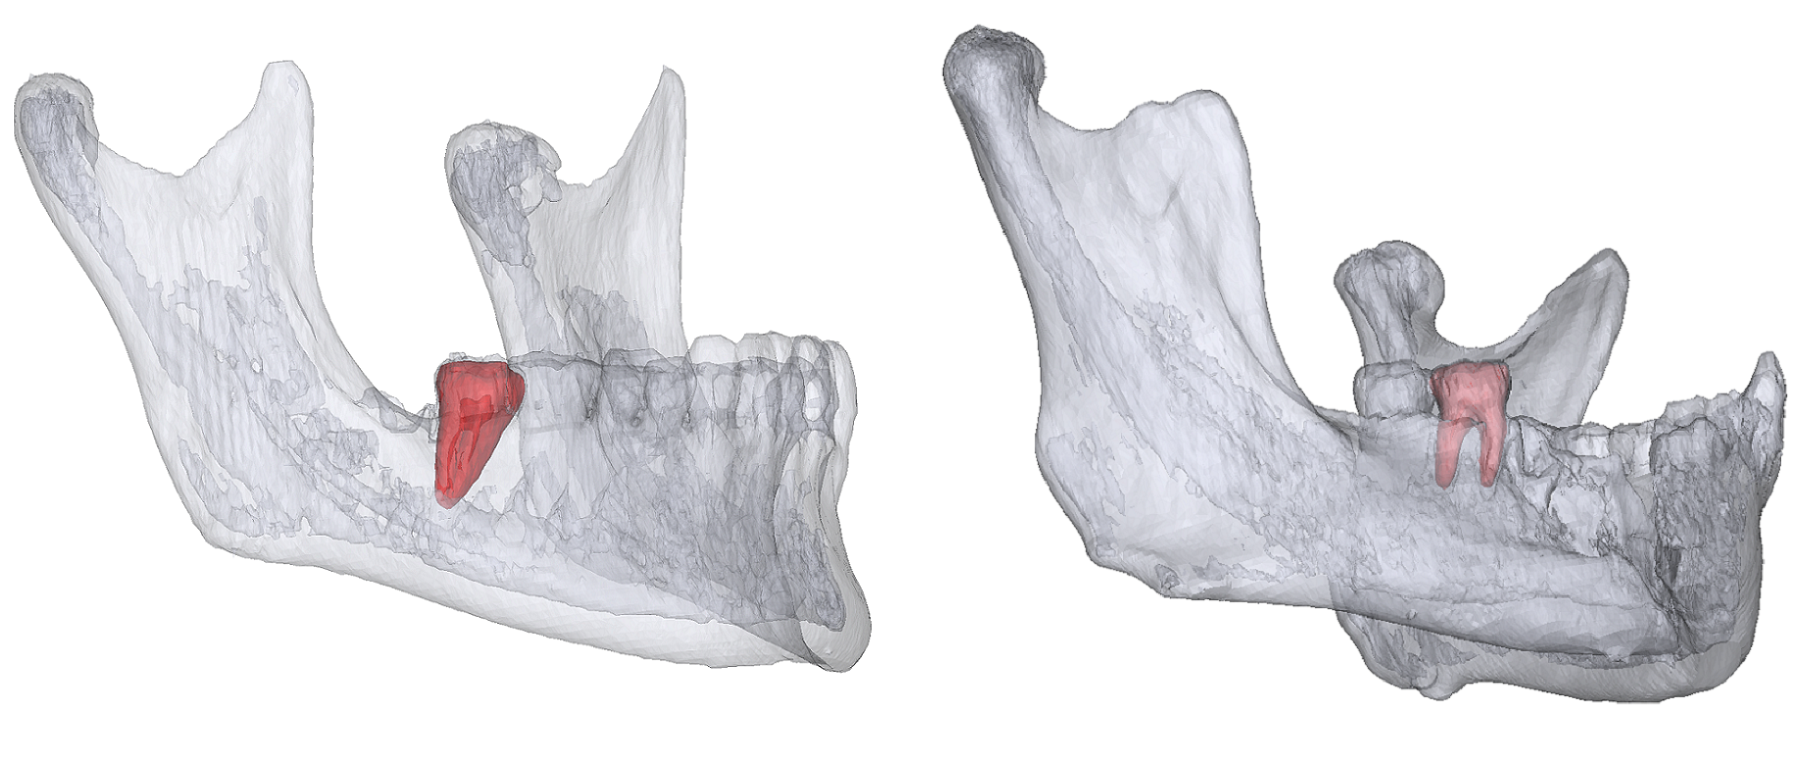

The project of Mandibular Molar Landmarking (MML) aims to identify the anatomy locations of the second and third mandibular molars' crowns and roots. The task has two main challenges:

Mandibular molars have different root numbers because of molars' variant growth.

Mandibular molars can be damaged by dental diseases, trauma, or surgery.

- MML requires models that are robust in clinical environments and are capable of detecting arbitrary landmarks on pre-operative or post-operative CT volumes, meeting real clinical needs.